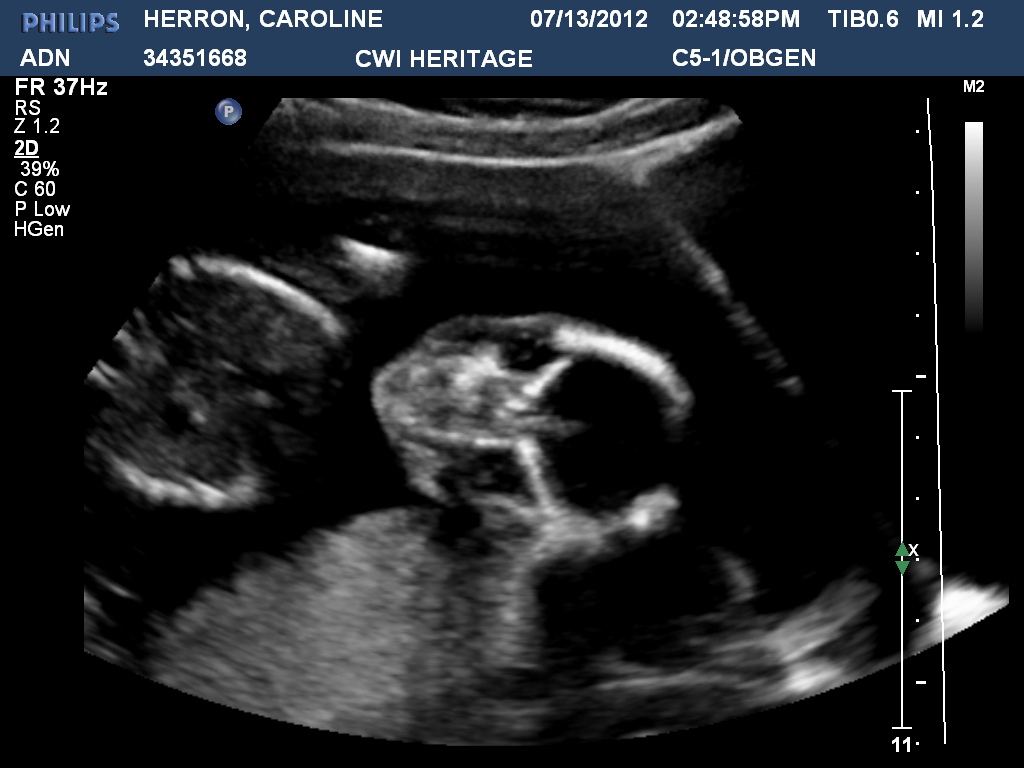

All of this will be faithfully recorded in our little baby book but... here goes! A lot of people were so confused when they saw this picture so I'll try to help. You're looking at two bent legs from the tail bone up. See it now? Amazing! My day began at our Back To School Bash with work. We invited all of our patients to come to a fun center and celebrate so around 500 showed up! We had a lot of fun but needless to say, I was ready to be at our appointment. So, Blake and his wonderful mother and sister came to pick me up and we drove to Nashville. After the appointment I had a divine appointment with our women's ministry. I was in charge of a women's event at church and it was spectacular! My friend and coworker Christina came and brought the word! Oh, so many gifts in one day!

The ultrasound tech didn't really give us any idea of how long this appointment would last so I assumed it would be like the previous ultrasound; quick. Nope. This ultrasound was a full twenty minutes! Can you believe she didn't give us the sex of little Herron until around minute seventeen? I mean I was praisin' the Lord for the brain, kidneys, mouth, nose, ribs, tailbone foot, bladder, and umbilical cord, but ...I wanted to picture pink or blue! She asked us at the end if we were "finding out" and we both exclaimed "well, YES!" We were cracking up with excitement. She ended up giving us a dvd of the entire ultrasound and you can hardly enjoy it because of all my giggles. Giggles turn into shakes on the screen! Poor baby is having to witness all these giggle earthquakes!

We received a very positive or what you'd call perfect report. Our doctor said that baby's legs are on the longer scale!!! I know it may not really mean anything yet but I'm glad to hear that baby may not have acquired my shortness! Also, baby's head is medium instead of large. GREAT NEWS for this momma. Everything else is just wonderful as well! I'm feeling our little babe move around and it's just a wonder. Wow! Praising the Lord!